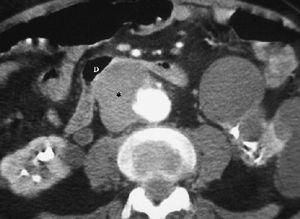

La forma más frecuente es la ausencia de rotación intestinal, que implica importantes alteraciones anatómicas valorables tanto en la ecografía como por la TC. Los principales hallazgos radiológicos son: alteración en la posición del duodeno, que no pasa entre la aorta y la arteria mesentérica superior (AMS); la localización en el hemiabdomen derecho de las asas de intestino delgado y en hemiabdomen izquierdo las de intestino grueso, y una verticalización o inversión de los vasos mesentéricos respecto a su posición normal, quedando la AMS a la derecha y la vena mesentérica superior (VMS) a la izquierda1,2 (fig. 1).

Fig. 1--Malrotación intestinal. (A) y (B) Tomografía computarizada con contraste oral e intevenoso mostrando inversión de la arteria mesentérica superior (AMS) (punta de flecha) y la vena mesentérica superior (flecha). La tercera porción duodenal (D) no cruza la línea media entre la aorta y la AMS, localizándose las asas de yeyuno a la derecha.